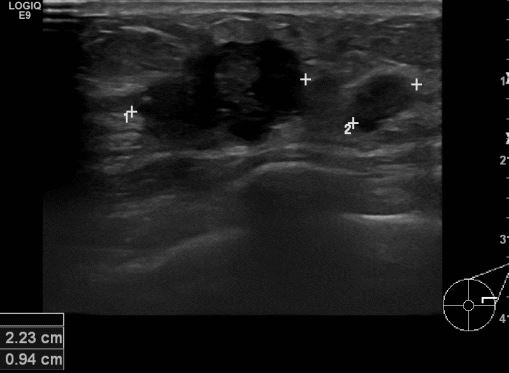

상기환자 건강검진상 이상 소견으로 내원하신 50대 여성분으로  좌측 3시 방향에

의심스러운 멍울 조직검사 시행하여 좌측 침윤성 유관암 진단 되었습니다.